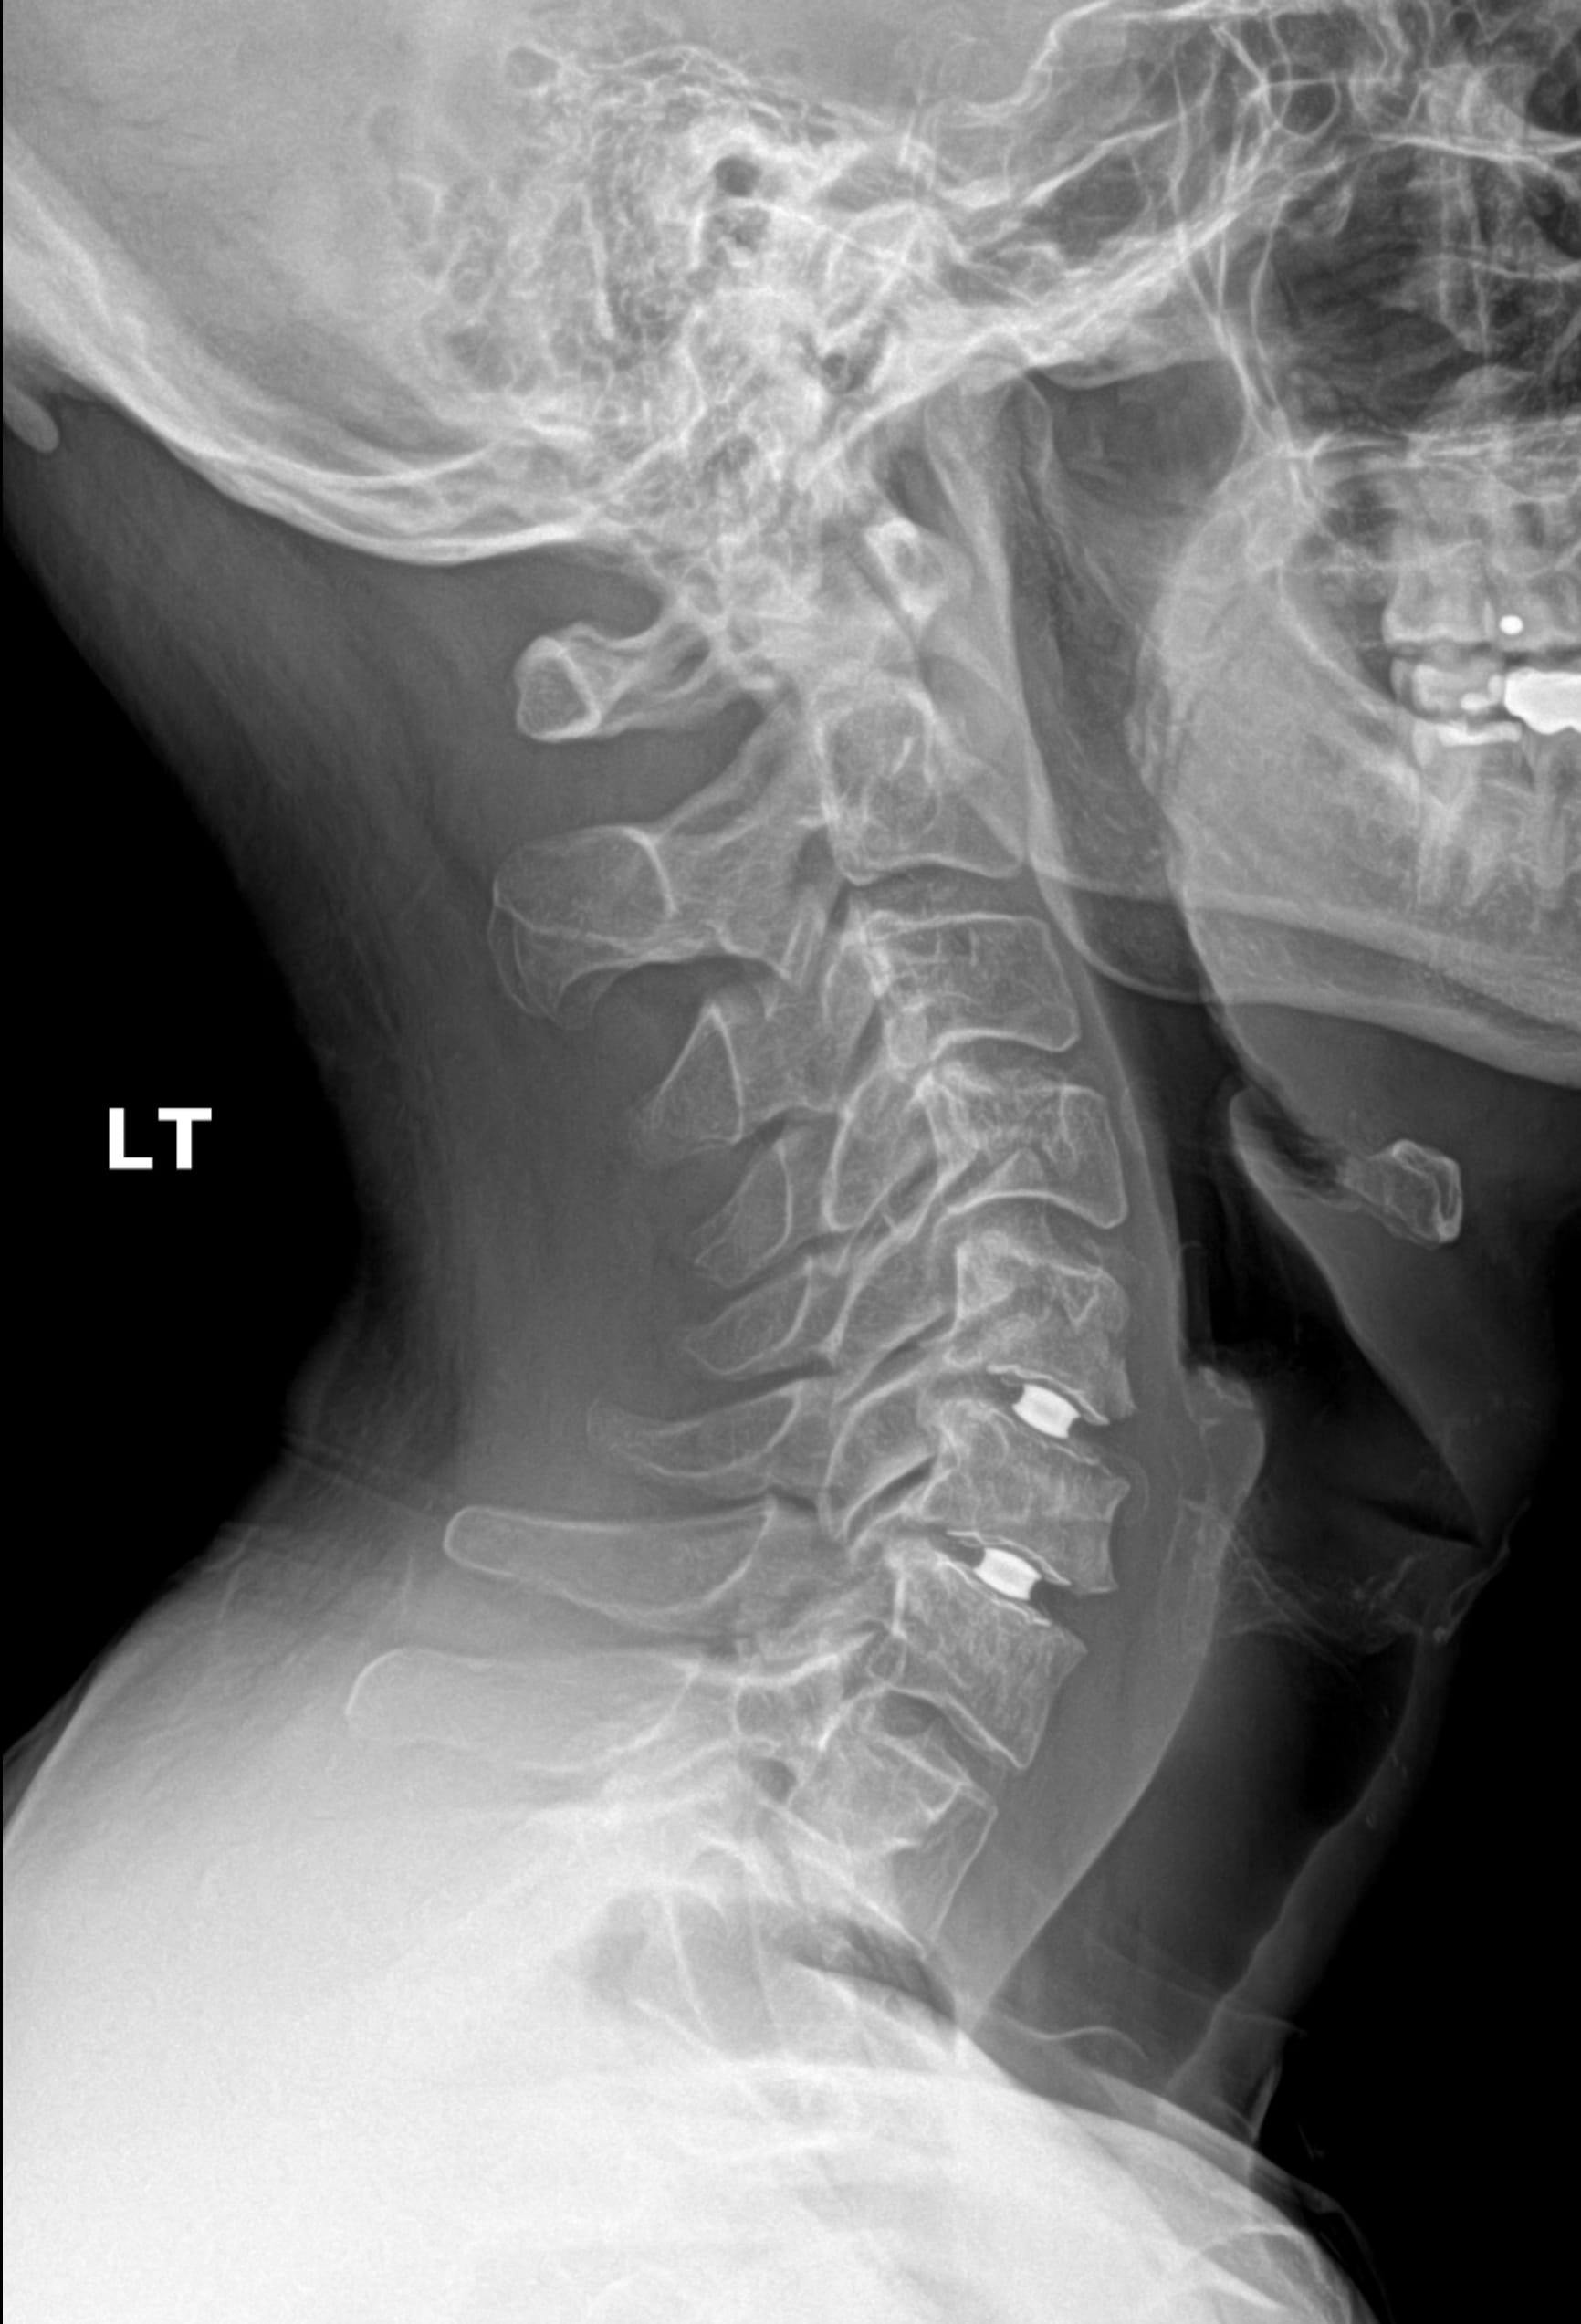

If you're considering cervical disc replacement in New Jersey, the Simplify Cervical Disc may be suited to you if: